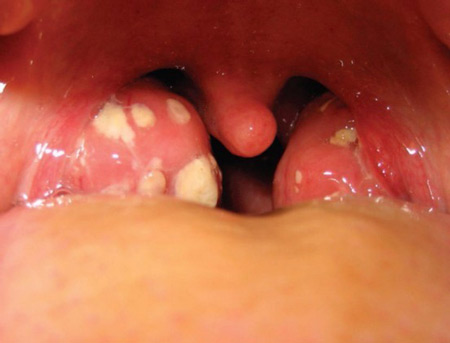

Чаще всего (90% случаев)белые точки на гландах оказываются гнойными комочками, возникающими из-за лакунарной ангины.

Белые пятна — это образовавшиеся на миндалинах комочки небольшого размера, имеющие белый или желтый цвет. Их можно разглядеть невооруженным глазом перед зеркалом, широко раскрыв рот.

Они имеют густую консистенцию и состоят из гноя и белых кровяных телец — погибших микроорганизмов.

Гланды имеют пористую поверхность. Углубления, имеющиеся на них, называются лакунами. В лакунах задерживаются микробы и вирусы. При нормальной работе иммунной системы вредоносные бактерии уничтожаются организмом.

Если иммунитет человека снижен, то появляются белые пятна на миндалинах, свидетельствующие о нарушениях в организме человека.

- белые точки на одной миндалине или сразу на обеих;

- Красное горло. Покраснение горла является одним из признаков заболевания. Иногда, на миндалинах в горле образовываются маленькие белые точки или пятна;

Стоит отметить, что существует несколько видов ангины, в зависимости от типа этого заболевания на миндалинах могут образовываться белые точки или пятна, имеющие различный оттенок. Цвет налета может варьироваться от белого до серого и даже коричневого.